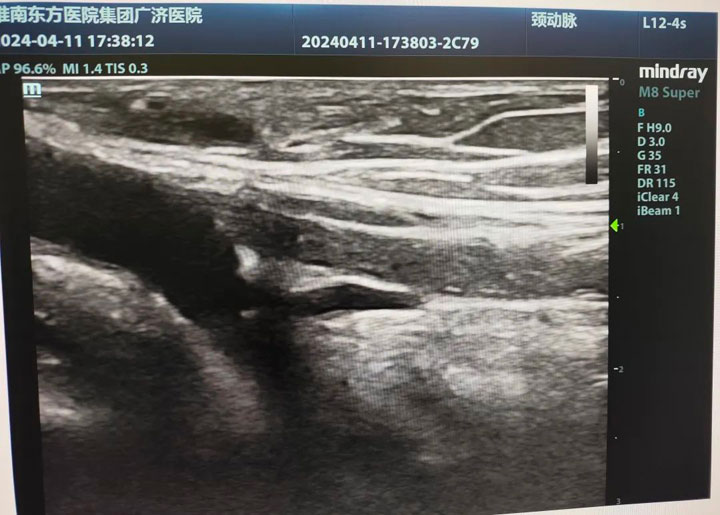

▲血栓闭塞2年的桡动脉

作为一名专业的透析通路医生,魏然主任首先为其详细评估两侧动静脉内瘘,彩超探查,右前臂动静脉内瘘大量血栓形成,左前臂动静脉内瘘血栓形成。急查双上肢动、静脉+多普勒血流图:右侧动静脉内瘘吻合口至头静脉弓锁骨下静脉汇入点处全段血栓形成。左侧桡动脉闭塞,左侧前臂头静脉血栓形成。

“左侧老瘘前臂桡动脉、头静脉血栓,右侧新瘘血栓形成距离更长,贵要静脉、上臂头静脉、锁骨下静脉都不乐观。”考虑到患者远期通畅率及经济压力等问题,魏然主任为患者制定了两套手术方案,首选打通左前臂血栓闭塞2年的“老瘘”。完善术前准备后,魏主任第一时间安排手术,在无影灯下,他手持超声探头,熟练操作,一点一点清除血栓开通闭塞,终于闭塞2年之久的内瘘再通了。“虽然难度大,但是手术顺利,放心吧。”